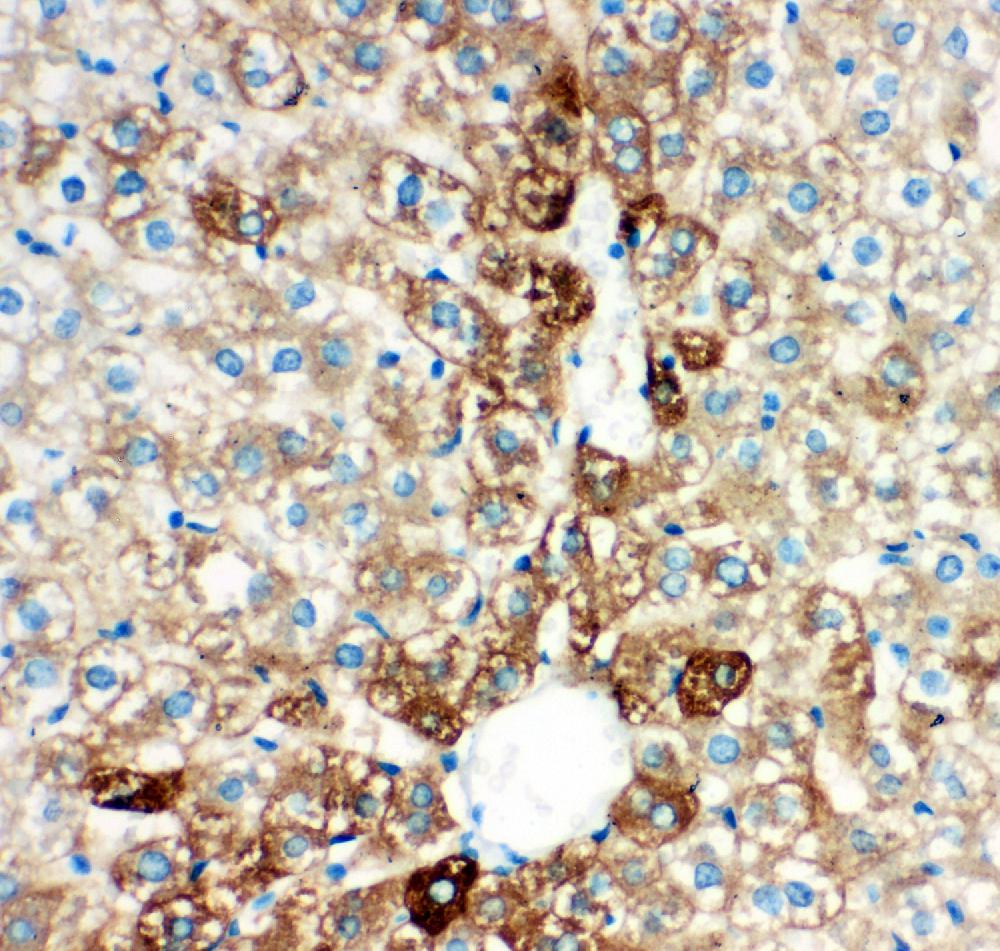

IHC analysis of CYP2E1 using anti-CYP2E1 antibody (PB9190).

CYP2E1 was detected in a paraffin-embedded section of rat liver tissue. Biotinylated goat anti-rabbit IgG was used as secondary antibody. The tissue section was incubated with rabbit anti-CYP2E1 Antibody (PB9190) at a dilution of 1:200 and developed using Strepavidin-Biotin-Complex (SABC) (Catalog # SA1022) with DAB (Catalog # AR1027) as the chromogen.